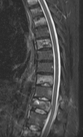

Lomber dinamik stabilizasyon

Ağustos         2022     Lomber enstruman yetmezliği ve dinamik stabilizasyonla çözümü